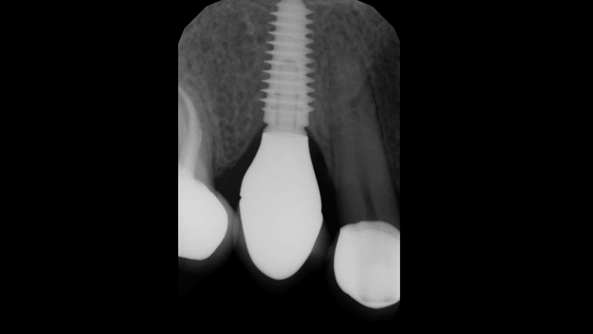

Clinical case: Digital Data Save concept in upper jaw premolar area

- Courtesy of Dr. Lysov Alexander Dmitrievich & Dr. Sofronov Matvey Vitalievich, Russia -

AnyRidge, R2GATE, R2GATE guide, ISQ value, initial stability, immediate loading, KnifeThread, maxillary posterior, #14, Digital, Dr. Lysov Alexander Dmitrievich, Dr. Sofronov Matvey Vitalievich, zirconia abutment, CAD/CAM crown

“AnyRidge & R2GATE show stable results

after immediate extraction, immediate implant placement, & immediate loading,

even with low bone density.”